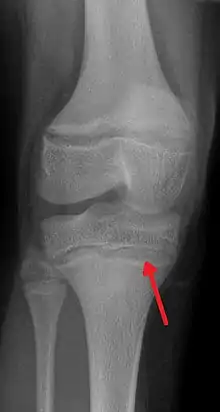

![]() | |

| An X-ray demonstrating the characteristic finding of lead poisoning in humans—dense metaphyseal lines | |

Exposure to lead can occur by contaminated air, water, dust, food, or consumer products.[2] Lead poisoning poses a significantly increased risk to children as they are far more likely to ingest lead indirectly by chewing on toys or other objects that are coated in lead paint.[2] The amount of lead that can be absorbed by children is also higher than that of adults. Exposure at work is a common cause of lead poisoning in adults with certain occupations at particular risk.[7] Diagnosis is typically by measurement of the blood lead level.[2] The Centers for Disease Control and Prevention (US) has set the upper limit for blood lead for adults at 10 µg/dl (10 µg/100 g) and for children at 3.5 µg/dl,[8] previously before October 2021 5 µg/dl[9][10] Elevated lead may also be detected by changes in red blood cells or dense lines in the bones of children as seen on X-ray.[4]

Blood lead levels are an indicator mainly of recent or current lead exposure, not of total body burden.[208] Lead in bones can be measured noninvasively by X-ray fluorescence; this may be the best measure of cumulative exposure and total body burden.[37] However, this method is not widely available and is mainly used for research rather than routine diagnosis.[103] Another radiographic sign of elevated lead levels is the presence of radiodense lines called lead lines at the metaphysis in the long bones of growing children, especially around the knees.[209] These lead lines, caused by increased calcification due to disrupted metabolism in the growing bones, become wider as the duration of lead exposure increases.[209] X-rays may also reveal lead-containing foreign materials such as paint chips in the gastrointestinal tract.[26][209]